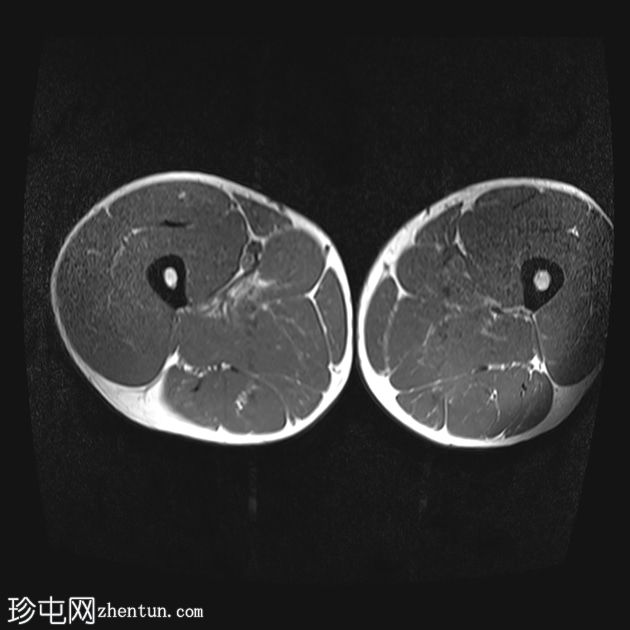

轴位

T1加权像

内收长肌和内收短肌中远侧外侧可见羽状改变和肌内水肿,主要累及内收大肌,长15厘米,宽4厘米。未见明显血肿或完全性肌纤维撕裂。

后腱膜、邻近神经血管交界处及邻近肌间隙可见积液,少量积液向外侧扩散,沿肌间隙到达大腿中远侧。

内收肌腱完整,骨性附着点清晰可见,肌腱轻度增厚,中部可见腱周水肿;未见撕裂。

影像学特征符合英国田径肌肉损伤分级(BAMIC/BAC)2B级损伤,主要累及大收肌。未见明显的血肿或肌纤维完全撕裂。

后侧腱膜、邻近神经血管束及肌间隙可见积液,少量积液沿肌间隙向外侧延伸至大腿中远端。